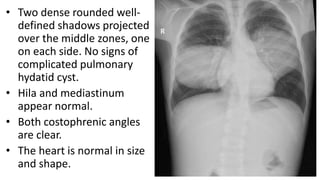

• Two dense rounded well-

defined shadows projected

over the middle zones, one

on each side. No signs of

complicated pulmonary

hydatid cyst.

• Hila and mediastinum

appear normal.

• Both costophrenic angles

are clear.

• The heart is normal in size

and shape.